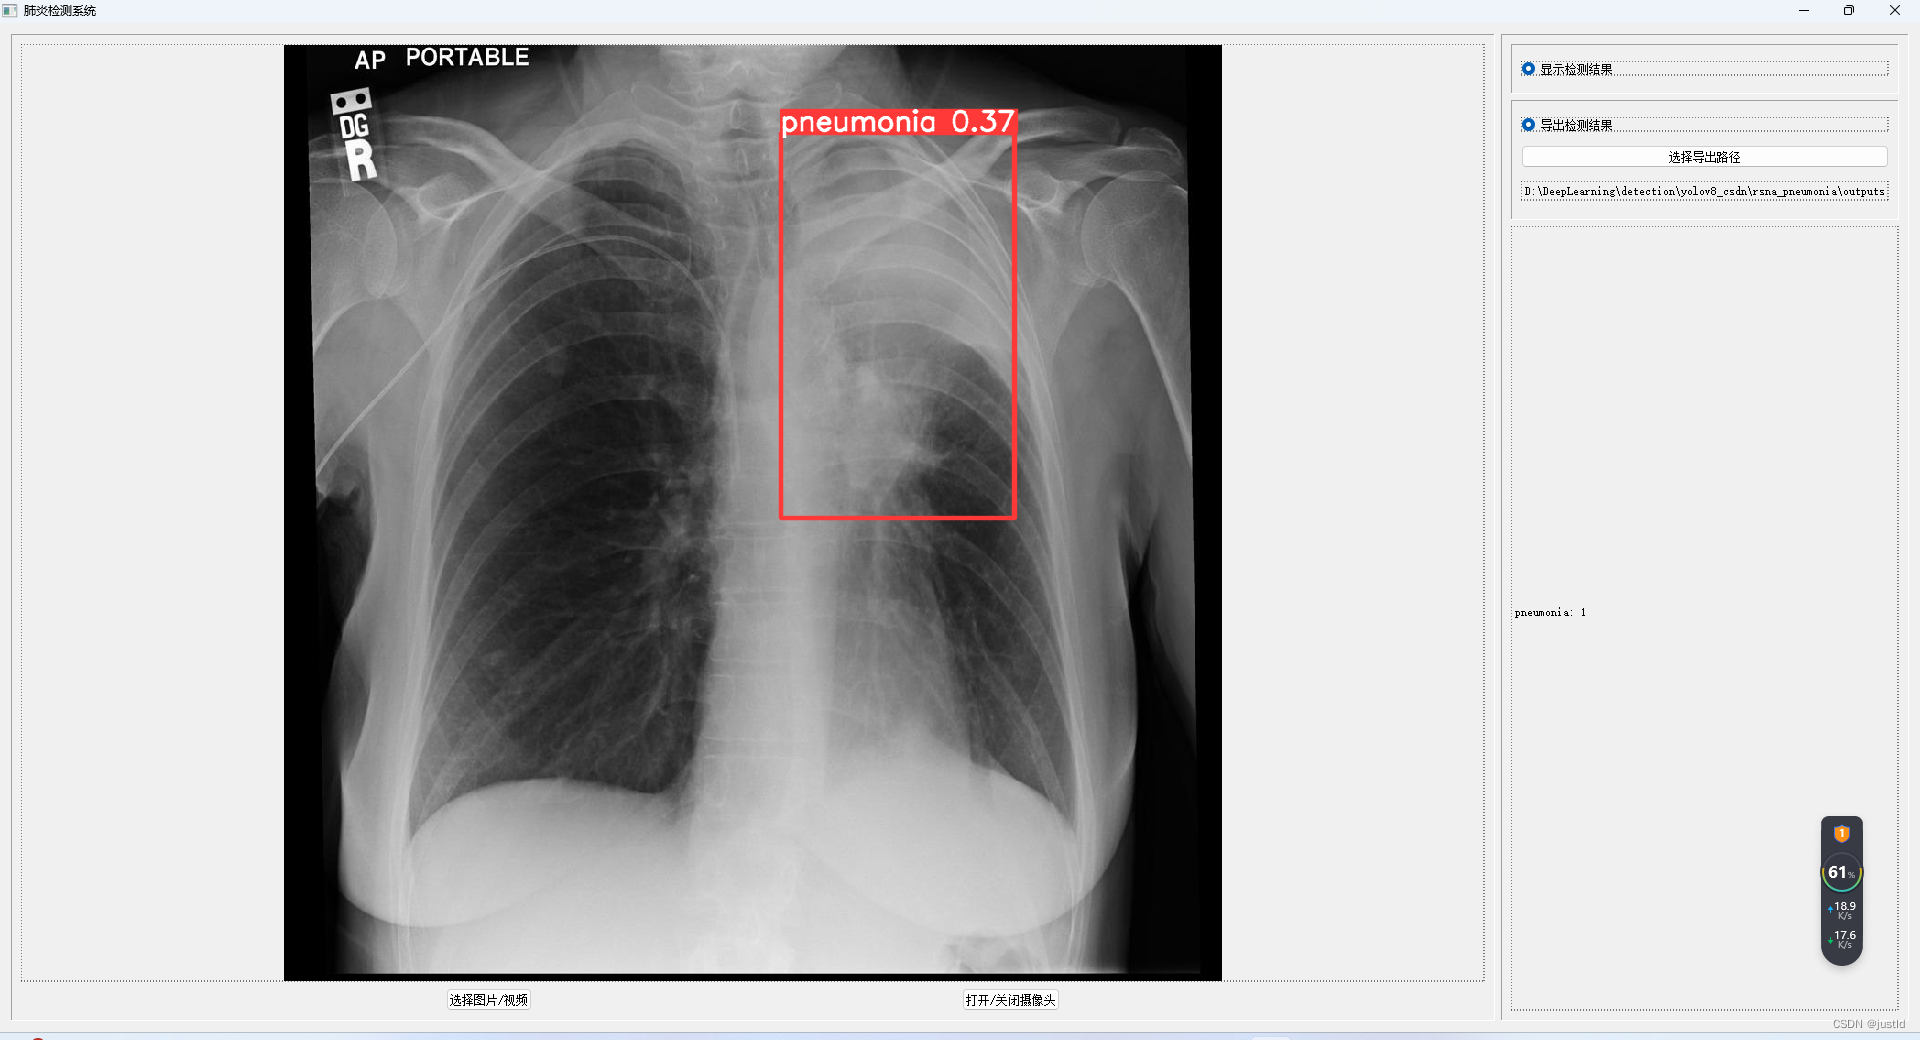

检测结果如下图:

使用pyqt5开发gui界面,支持图片、视频、摄像头输入,支持导出到指定路径,其GUI如下图(完整GUI代码可在下方链接下载):